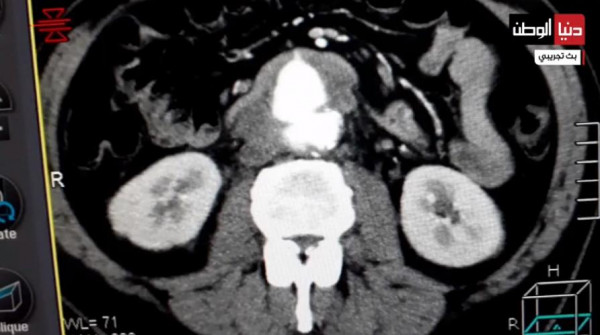

وأضاف أنه تم نقل أكثر من 20 وحدة دم للمريض خلال العملية، وأن المريض خضع لعدة كورسات من المضادات الحيوية الواسعة الانتشار ومن ثم أجريت له صورة مقطعية تبين هدم وجود أي مضاعفات خلال فترة التعافي التي تمت تحت المراقبة الطبية وخرج من المستشفى بعد أسبوعين من إجراء العملية في أتم صحة وبدون مضاعفات.